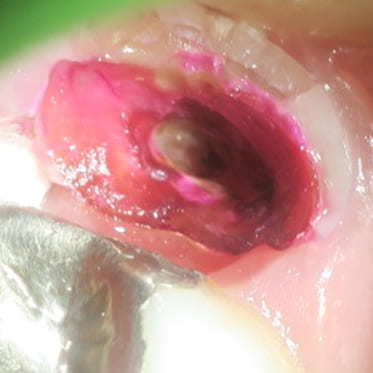

歯を抜かない治療(C4)

不幸にも、虫歯が進行して骨に埋まっている部分の歯(歯根)まで細菌感染が起こってしまった場合(C4)、通常では抜歯が適応治療になります。 しかし、歯根まで虫歯が進行してしまっている場合の多くは痛みが無いのも特徴です。 特に痛みも無いのになんで歯を抜かなければならないかとお思いの患者様も多くいらっしゃいます。 生物学的・医学的には抜歯が適応であったとしても、患者様のご希望と、精密検査の結果から、当院では歯を抜かずに温存する治療も行っております。 もう歯がほとんど残っていないから歯を抜かなければならないと諦めていらっしゃる患者様も、ぜひ一度当院にてご相談、検査をさせて下さい。